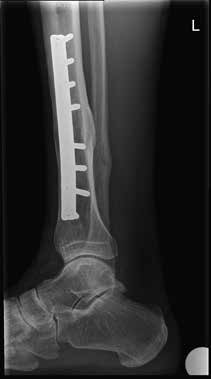

Dem Patienten wurde eine orthopädische Innenschuhorthese als Versorgung vorgeschlagen (Abb. 2). Um diese zu testen, wurde dem Patienten ein abnehmbares Soft-Cast-Stiefelchen (Abb. 3 und 4) mitgegeben. Dieses konnte sofort angefertigt werden und zeigte unmittelbar den gewünschten Erfolg, sodass die vorgeschlagene Versorgung nach kurzer Zeit ausgeführt werden konnte (Abb. 5).

Das Resultat ist sehr erfreulich: Der Patient kann ohne Schmerzmitteleinnahme wieder bis zu sechs Stunden wandern und fühlt sich im unebenen Gelände wieder deutlich sicherer. Einzig das Gehen am Berg bereitet ihm wegen des relativ blockierten oberen Sprunggelenkes mehr Mühe als früher.